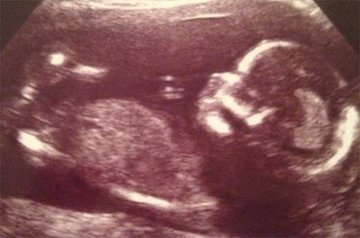

اما یک مادر باردار بزرگترین شوک زندگی خود را زمانی تجربه کرد که برای سونوگرافی به پزشک مراجعه کرده بود. اما تصویر نوازاد به دنیا نیامدهاش تنها چیزی نبود که او روی صفحه مانیتور دید. بلکه تصویر اردکی در کنار جنین تعجب او و دکترش را برانگیخت.

کورتنی فنویک ۲۸ ساله اهل نیوکاسل مادری بود که شاهد این تجربه بود. او بعد از ۳ سال مشکل بارداری و ۳ بار آی وی اف که با مشکل مواجه شده بود، دوباره باردار شد. این بارداری با توجه به اینکه مادر دچار دیابت شد بسیار سخت بود. اما حضور این اردک اسباب خنده آنها را فراهم کرد.

حضور این اردک تنها این والدین بلکه دکتران دیگر را هم شگفتزده کرده بود وآنها میگفتند تاکنون نه چنین چیزی دیدهاند نه شنیدهاند.

اکنون این نوزاد به دنیا آمده و در کمال صحت و سلامت به سر میبرد. هنگام زایمان خبری از اردک فوقالذکر نبود. اما دوستان به یاد آن اردک برای نوزاد به دنیا امده عروسک اردک آوردند. پزشکان هم نتوانستند توجیه مناسبی برای حضور اردک پیدا کنند.